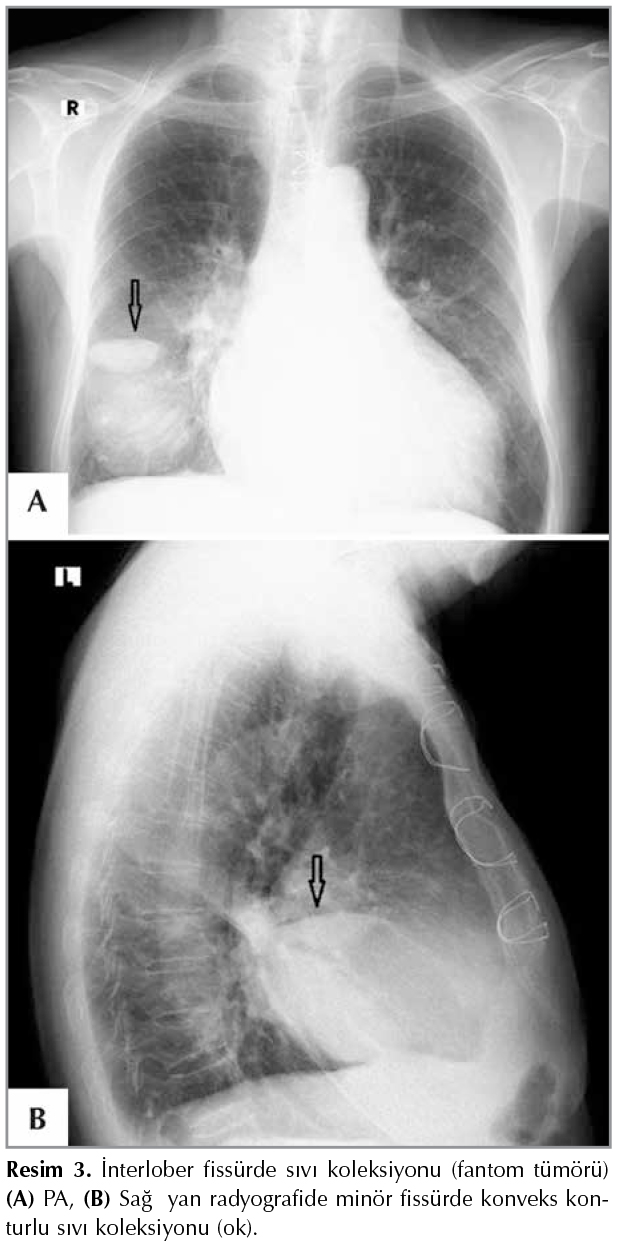

Hidatik kist nadiren plevral boşlukta ve interlober fiss?rde lokalize olmaktadır (primer plevral hidatidozis). Evcil k?peklerin neden olduğu hidatik kistle infekte olgularda sık g?r?lmemektedir (36). Plevral boşlukta ve interlober fiss?rdeki intakt hidatik kist PA radyografide homojen yoğunluk artışı g?stermektedir (Resim 11). USG'de ekoik kaps?ll? sıvı i?eren anekoik kistik lezyon şeklinde g?r?lmektedir. BT'?de diğer organlarda g?r?len bulgulara benzer şekilde kaps?ll? sıvı i?eren d?ş?k dansiteli kistik lezyon şeklinde g?r?lmektedir. MR g?r?nt?leme yumuşak doku kontrast ?zelliğine bağlı olarak gerek plevral boşluktaki, gerekse interlober fiss?rdeki kistik lezyonu diğer y?ntemlere g?re daha ayrıntılı g?stermektedir (37,38). Plevral boşluktaki intakt hidatik kist spontan olarak veya travma nedeniyle perfore olabilir Germinatif membranın perikistten ayrılması ile perfore hidatik kist i?in olduk?a spesifik bulgu olan g?r?n?m meydana gelmektedir. Bu olgularda PA radyografide plevral ef?zyona benzer bulgu ve hava-sıvı seviyesi g?r?lebilir. Bu olgularda yumuşak doku kontrast ?zelliği ve ?? boyutlu g?r?nt?leme ?zelliği nedeniyle MRG daha ayrıntılı bilgi vermektedir (Resim 12) (37,38).

Resim 11